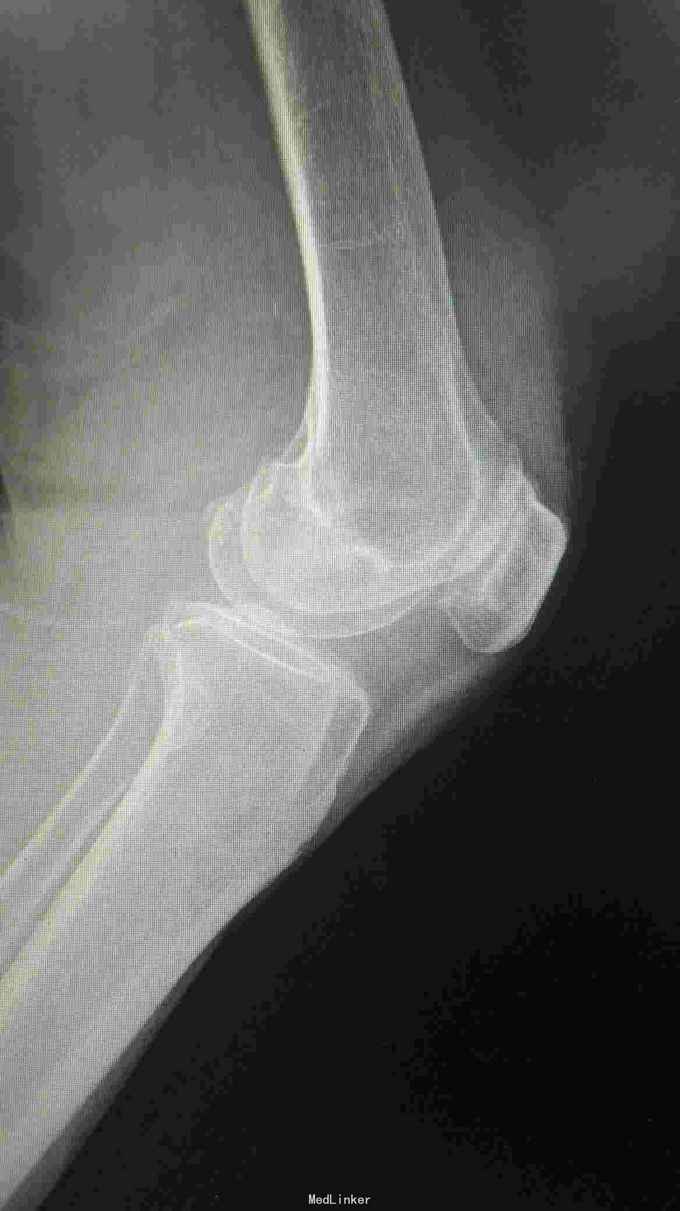

76岁女性,左膝关节疼痛5年,加重1月。平时以活动痛为主,最近一月疼痛明显,影响行走。既往体检。

左膝轻度内翻畸形,皮温稍高,膝关节前内侧压痛阳性,内外侧方应力试验阴性,前后抽屉试验阴性。屈伸活动度0---110度。 入院辅助检查:血常规、ESR、CRP、PCT均在正常范围。心肺功能可。

诊断:左膝关节骨性关节炎 治疗:左膝关节单髁置换术